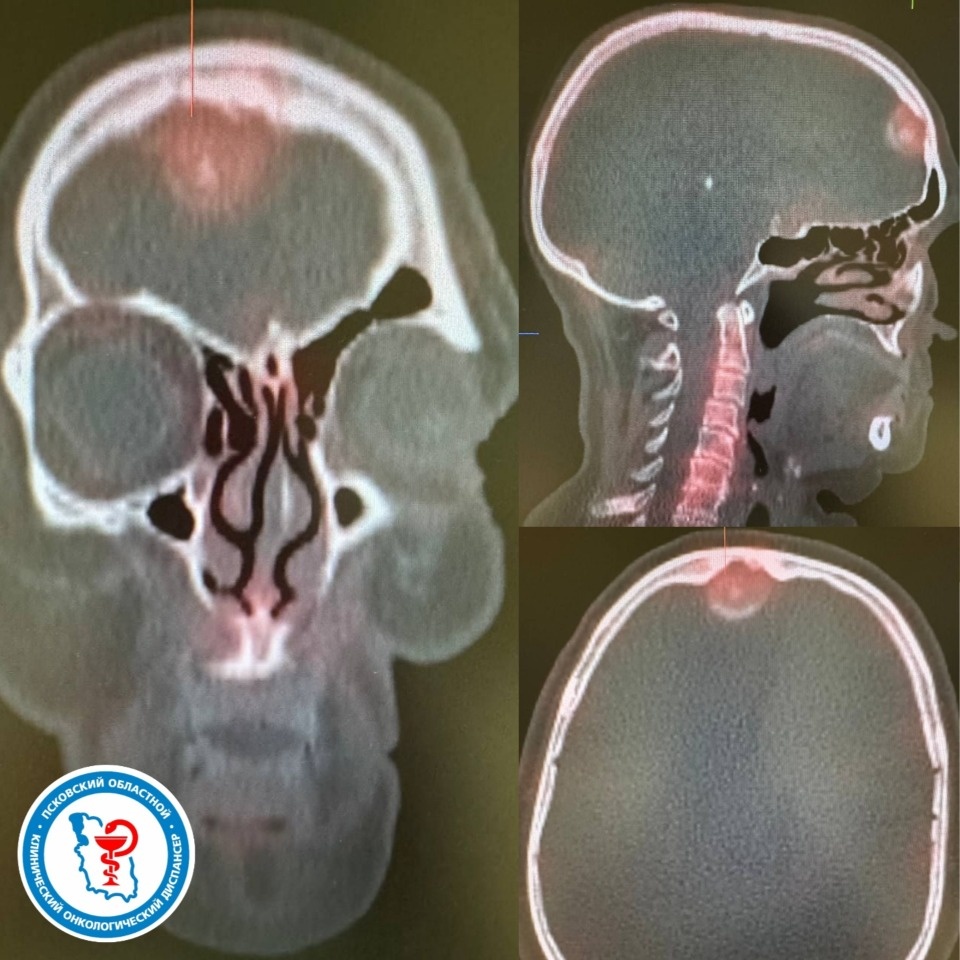

Симптомы, особенно жалобы на боли в костях, могли указывать на метастазы. Онколог назначил пациентке дополнительное обследование, включающее сцинтиграфию. Благодаря этому и пациентки выявили очаг гиперфиксации радиофармацевтического индикатора в лобной области.

В ходе дальнейших исследований в лобной области головного мозга обнаружили новообразование – менингиому. Она оказывала давление на окружающие ткани и могла вызывать описанные пациенткой симптомы. Пациентку успешно прооперировали. В ходе операции радикально удалили опухоль, что улучшило состояние женщины.